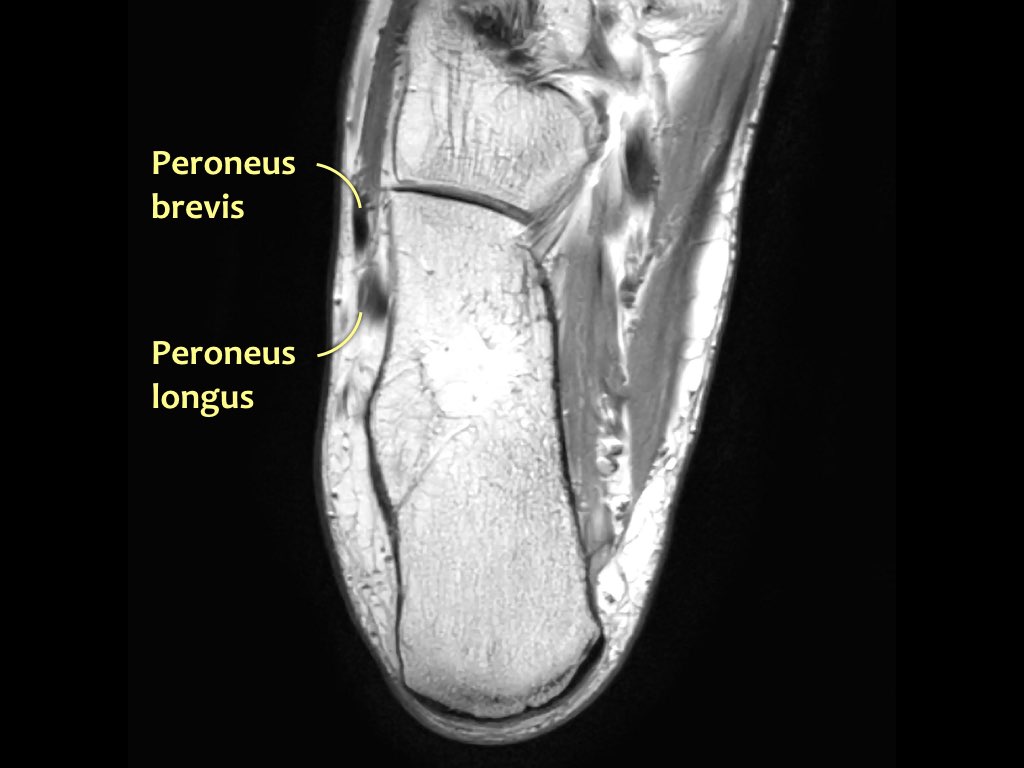

- Khoang ngoài

- Gân cơ mác dài (Peroneus Longus)

- Gân cơ mác ngắn (Peroneus Brevis)

Hướng đi của các gân dọc theo mắt cá trong và mắt cá ngoài có thể gây ra hiện tượng ‘xảo ảnh góc ma thuật’.

Các gân sẽ biểu hiện tín hiệu tăng tương đối khi tạo góc 55° so với B0, dễ nhầm lẫn với bệnh lý như viêm gân hoặc rách gân một phần.

Xảo ảnh này xuất hiện trên các chuỗi xung có thời gian TE ngắn (ví dụ: PD).

Trên các chuỗi xung có TE dài (như T2), xảo ảnh này cũng xuất hiện nhưng ít rõ rệt hơn.